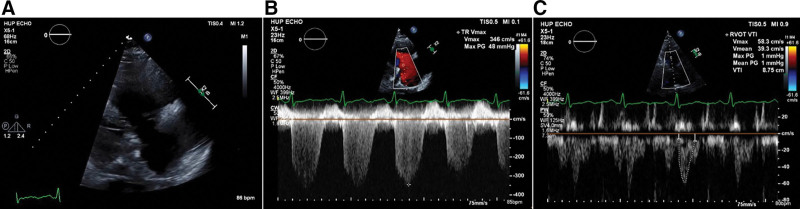

Abstract Image